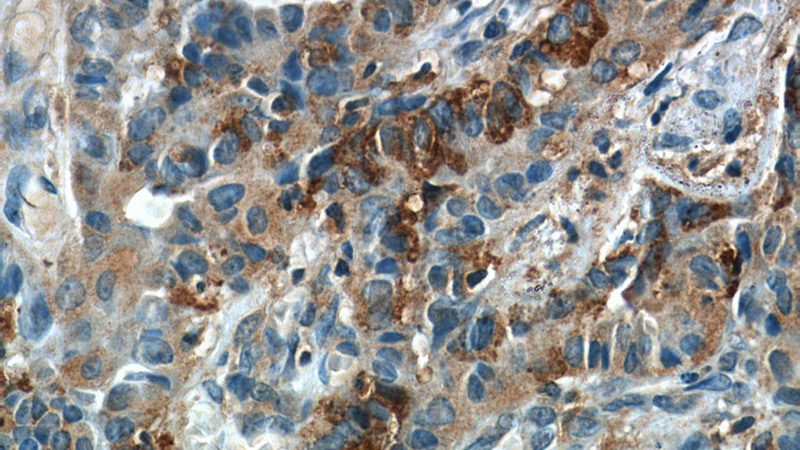

Immunohistochemistry of paraffin-embedded human thyroid cancer slide using Catalog No:110470(FAM129A Antibody) at dilution of 1:50